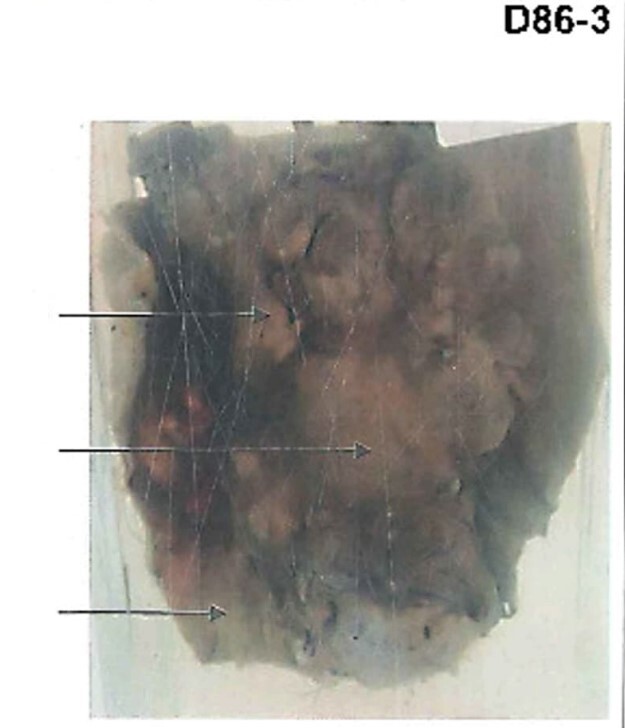

A slice of enlarged liver Dark areas (congestion) yellow areas (fatty changed) surface shows nutmeg appearance Caused by RS heart failure Chronic venous congestion of the liver